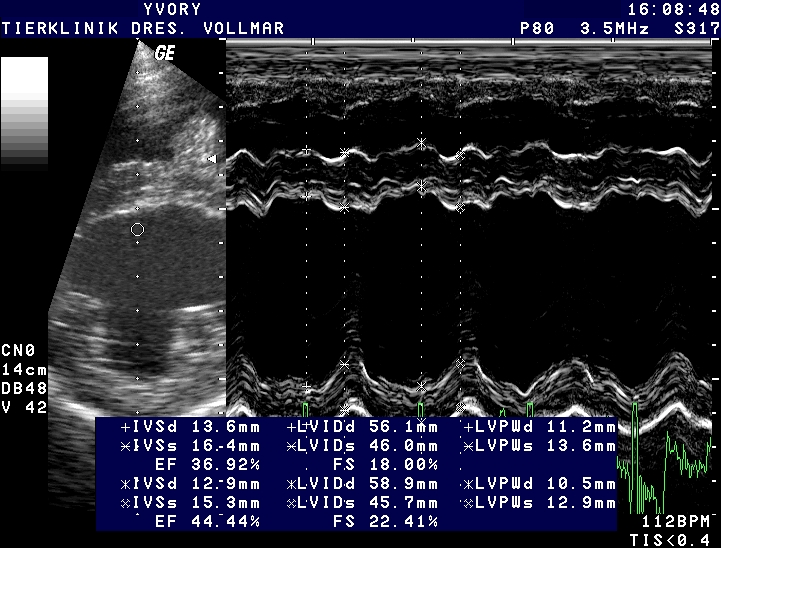

Dilatativen Kardiomyopathie (DCM)

Bei der dilatativen Kardiomyopathie (DCM) ist die Herangehensweise anders als bei MI. Die DCM tritt bei vielen größeren Hunderassen als Erberkrankung auf und unterscheidet sich bei verschiedenen Hunderassen in vielerlei Hinsicht, so auch im klinischen Erscheinungsbild und im Verlauf. Als auskultatorisch hinweisende Befunde kommen bei einigen Rassen zwar früh im Krankheitsverlauf Arrhythmien in Form von Extrasystolen oder Vorhofflimmern vor, häufig ist die Auskultation aber unauffällig. Leise Herzgeräusche entstehen erst spät im Krankheitsverlauf mit Entwicklung einer sekundären AV-Klappeninsuffizienz durch Dilatation des Anulus fibrosus und Papillarmuskelatrophie Daher basiert die Früherkennung allein auf der echokardiografischen Untersuchung, je nach Rasse ergänzt durch EKG-Befunde bis hin zum 24-Stunden Holter-EKG.

Besonders betroffene Rassen wie Dobermänner, Deutsche Doggen, Irische Wolfshunde, sollten ab dem jungen Erwachsenenalter regelmäßig kardiologisch untersucht werden - nicht nur aus zuchthygienischen Gründen, sondern auch, um dem Individuum möglichst lange eine gute Lebensqualität zu ermöglichen und die Lebenserwartung zu verbessern. Wie Erfahrungen aus der Humanmedizin und inzwischen mehrere veterinärmedizinische Studien zeigen, muss das vorrangige Ziel sein, die Erkrankung möglichst früh im präklinischen Stadium zu diagnostizieren und eine frühzeitige Therapie zu beginnen.